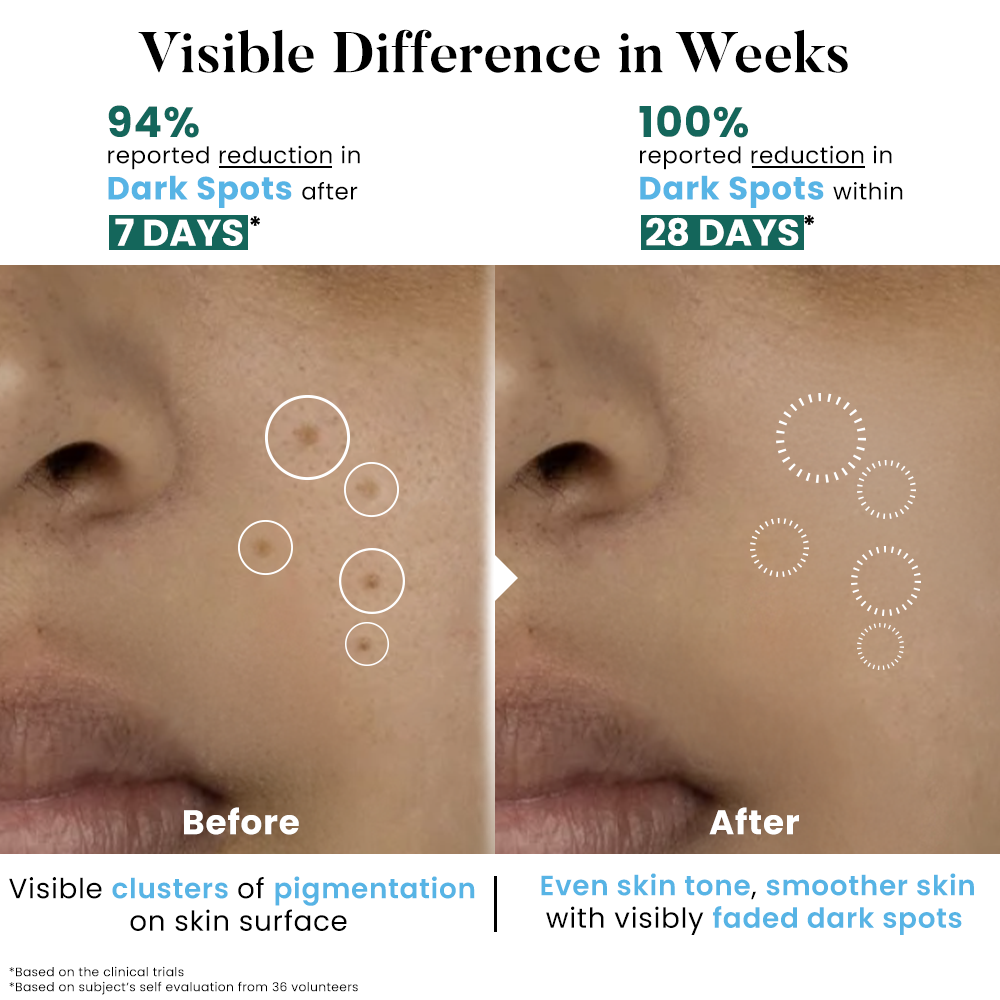

After 7 days

Before

After